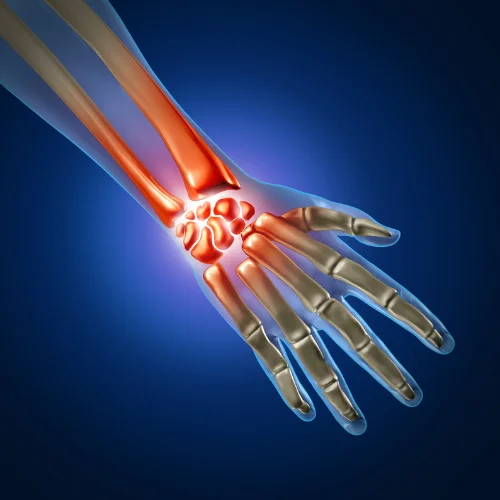

Hand and wrist surgery focuses on the diagnosis, treatment, and rehabilitation of conditions affecting the hand, wrist, and forearm. Whether caused by injury, arthritis, or repetitive strain, our expert orthopedic surgeons provide advanced surgical and non-surgical solutions to restore function, alleviate pain, and improve mobility.

This type of surgery, also called arthroplasty, is used in cases of severe hand arthritis. It is done by replacing a joint that has been destroyed by arthritis or injury with an artificial joint. This artificial joint may be made of metal, plastic, silicone rubber, or your own body tissue, such as a tendon.

Reduces or eliminates chronic joint pain.

Enhances movement and flexibility.